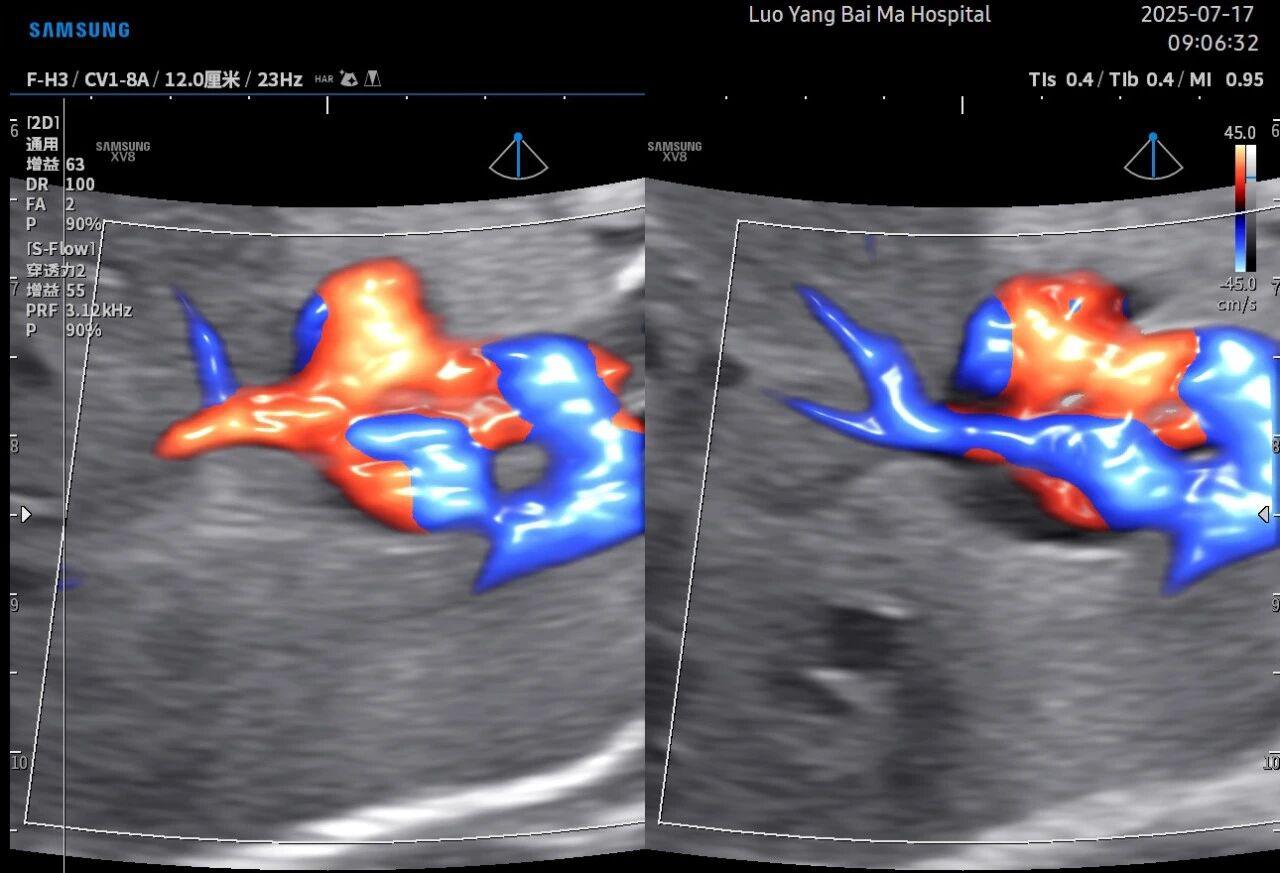

孕中期(通常在22-28周)的大排畸检查是整个孕期至关重要的环节之一。其目的在于系统地筛查胎儿是否存在结构性异常,如唇裂、脊柱裂、大脑、心脏、骨骼发育不良等问题。在这一关键检查中,5D智能彩超凭借其技术特性,展现出了显著的优势。

2. 全方位、多角度的“360度”观察

传统超声检查有时会因为胎儿体位、羊水量等因素的限制,导致某些部位观察不清。5D智能彩超技术能够实现对目标结构进行360°全方位、多切面的自由旋转观察。医生可以像“雕塑家”一样,从任意角度审视胎儿的解剖结构,尤其对于形态复杂的心脏、颅脑和脊柱等部位,这种能力可以极大弥补单一平面的局限性,帮助医生更全面地评估其发育状况。